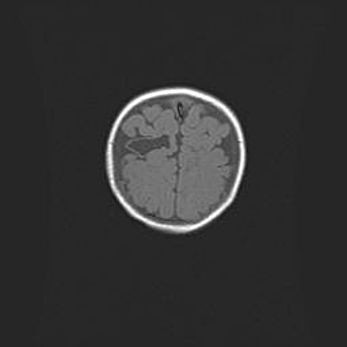

Лейкомаляция с кистозно-глиозной дегенерацией головного мозга.

Возраст: 2 месяца 25 дней

Вес: 6400 г

Окружность головы: 40 см

Срок гестации: 41 неделя

Лейкомаляцию относят к ишемически-гипоксическим повреждениям головного мозга, диагностируемым у новорожденных. При лейкомаляции в головном мозге обнаруживают очаги некроза, возникшие после тяжелой гипоксии и нарушения кровотока. В процессе морфогенеза очаги проходят три стадии: 1) развития некроза, 2) резорбции и 3) формирования глиозного рубца или кисты. Перивентрикулярная лейкомаляция (ПЛ) встречается примерно в 12% случаев среди новорожденных, обычно – у недоношенных детей, причем, частота ее зависит от массы, с которой младенец появился на свет. Наибольшее число малышей страдает лейкомаляцией, если масса при рождении 1500-2500 г.